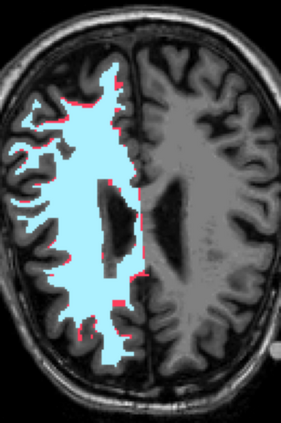

Deep neural networks for medical image reconstruction are traditionally trained using high-quality ground-truth images as training targets. Recent work onNoise2Noise (N2N) has shown the potential of using multiple noisy measurements of the same object as an alternative to having a ground truth. However, existing N2N-based methods cannot exploit information from various motion states, limiting their ability to learn on moving objects. This paper addresses this issue by proposing a novel motion-compensated deep image reconstruction (MoDIR) method that can use information from several unregistered and noisy measurements for training. MoDIR deals with object motion by including a deep registration module jointly trained with the deep reconstruction network without any ground-truth supervision. We validate MoDIR on both simulated and experimentally collected magnetic resonance imaging (MRI) data and show that it significantly improves imaging quality.